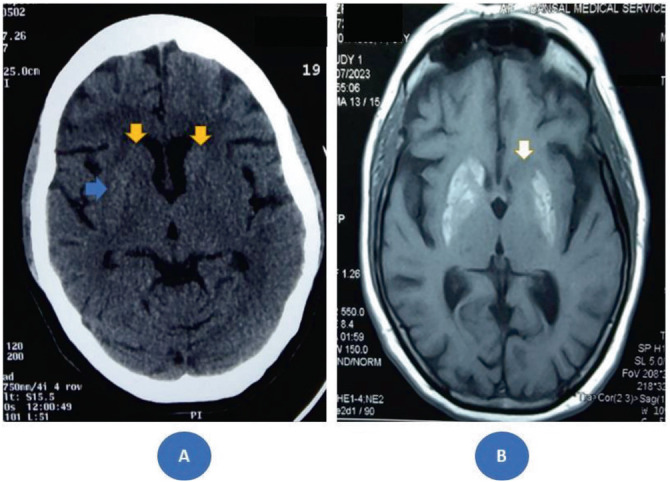

Case presentation: We present a case of DS in a 62-year-old woman from rural India with poorly controlled diabetes mellitus who developed acute-onset right hemichoreoballism. Neuroimaging revealed a predominantly right-sided striatal lesion, illustrating a clinicoradiological discordance-a mismatch between the clinical symptoms and radiological findings. Despite achieving tight glycemic control and administering neuroleptic medications, the involuntary movements demonstrated only partial improvement. Neurological changes persisted on the ipsilateral side of the affected limbs even after 1 year of follow-up. Notably, perioral dyskinesias developed during subsequent follow-up visits.